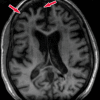

Neurodegenerative diseases are a devastating group of disorders that can be difficult to accurately diagnose. Although these disorders are difficult to manage owing to relatively limited treatment options, an early and correct diagnosis can help with managing symptoms and coping with the later stages of these disease processes. Both anatomic structural imaging and physiologic molecular imaging have evolved to a state in which these neurodegenerative processes can be identified relatively early with high accuracy. To determine the underlying disease, the radiologist should understand the different distributions and pathophysiologic processes involved. High-spatial-resolution MRI allows detection of subtle morphologic changes, as well as potential complications and alternate diagnoses, while molecular imaging allows visualization of altered function or abnormal increased or decreased concentration of disease-specific markers. These methodologies are complementary. Appropriate workup and interpretation of diagnostic studies require an integrated, multimodality, multidisciplinary approach. This article reviews the protocols and findings at MRI and nuclear medicine imaging, including with the use of flurodeoxyglucose, amyloid tracers, and dopaminergic transporter imaging (ioflupane). The pathophysiology of some of the major neurodegenerative processes and their clinical presentations are also reviewed; this information is critical to understand how these imaging modalities work, and it aids in the integration of clinical data to help synthesize a final diagnosis. Radiologists and nuclear medicine physicians aiming to include the evaluation of neurodegenerative diseases in their practice should be aware of and familiar with the multiple imaging modalities available and how using these modalities is essential in the multidisciplinary management of patients with neurodegenerative diseases.©RSNA, 2020.